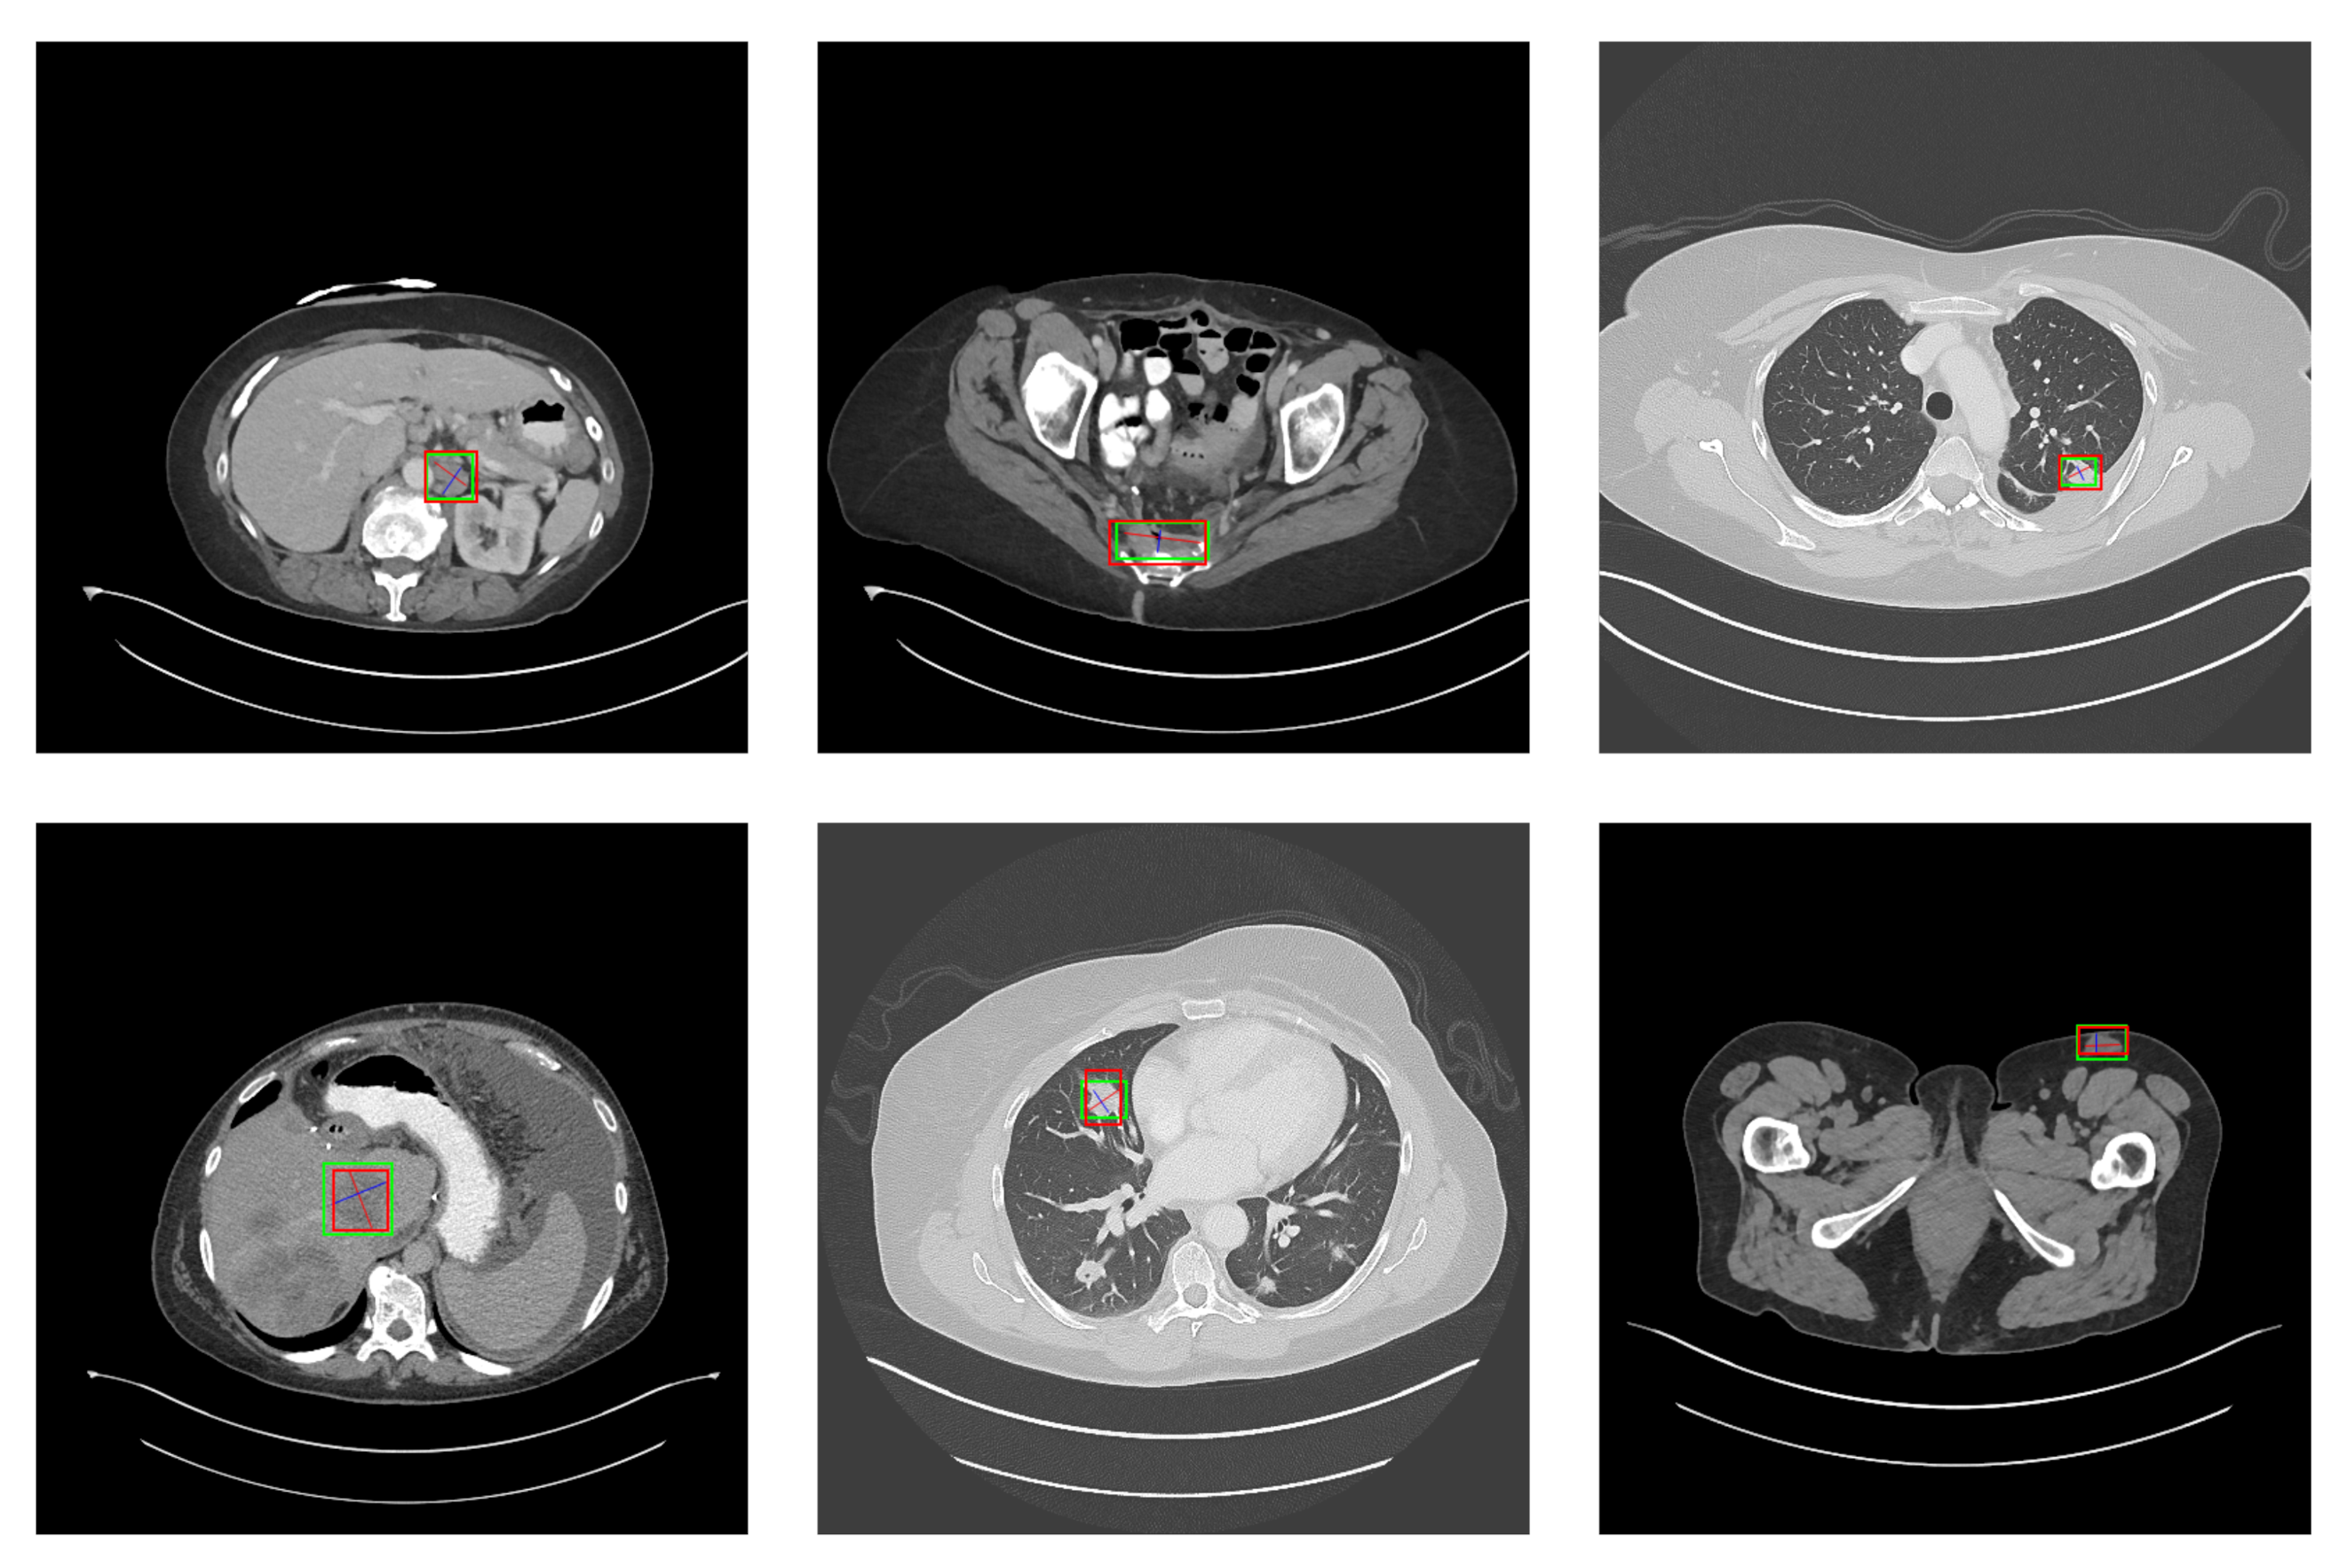

This paper employs a dataset that includes eight types of CT images: abdomen (lesions in the abdominal cavity that are not in the kidney or liver), soft tissue (various lesions in the body wall, such as fat, head, muscle, limbs, neck, and skin), liver, lung, mediastinum, bone, pelvis, and kidney. In Figure 1, it is demonstrated that the dataset has the following characteristics.

Figure 1.

Dataset visualization (the green box marks the location of the lesion). The following sample lesions are displayed to demonstrate the tremendous diversity of the dataset: (A) is a lung nodule; (B) is a lung cyst; (C) is costophrenic sulcus (lung) mass/fluid; (D) is a breast mass; (E) is a liver lesion; (F) is a renal mass; (G) is a huge abdominal mass; (H) is a posterior thigh mass; (I) is an iliac sclerotic lesion; (J) is a perirectal lymph node (LN); (K) is a pelvic mass; (L) is a periportal LN; (M) is an omental mass; (N) is a peripancreatic lesion; (O) is a splenic lesion; (P) is a subcutaneous/skin nodule; (Q) is opacity of ground glass; (R) is an axillary LN; (S) is a subcarinal LN; (T) is vertebral body metastases; (U) is a thyroid nodule; (V) is a neck mass.